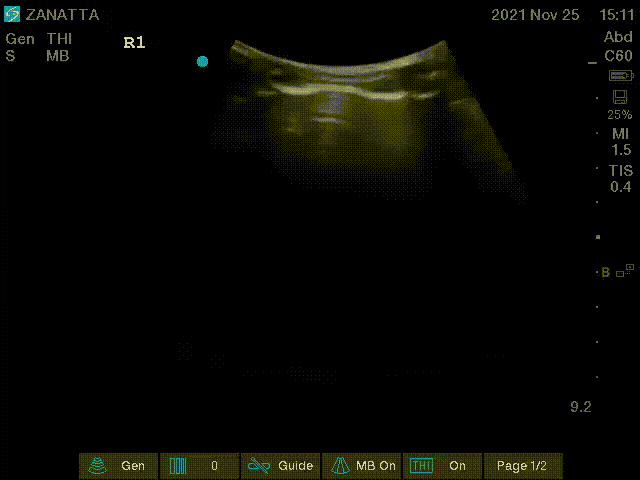

You begin your POCUS assessment with imaging of the left and right lungs.

Right Lung Views